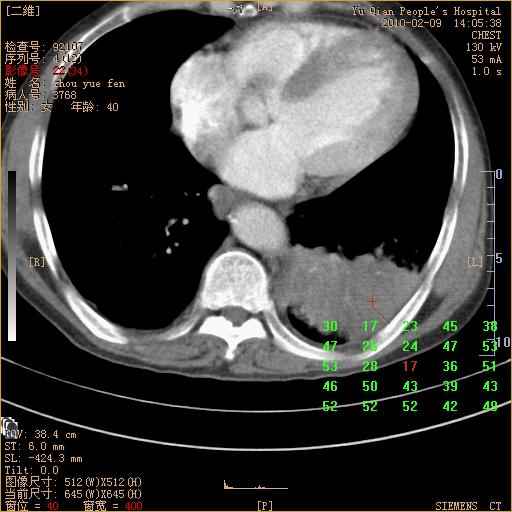

男性,73岁,咳嗽咳血数天,诊为肺ca伴左肺下叶后段阻塞性炎症、肺不张妥否?

右下肺有转移?

左下肺中央型肺癌伴结段形肺不张,左侧胸腔积液,纵隔内见部分增大淋巴结(反应性增生或转移)

左下基底干支气管明显变窄。

左肺下叶基底段支气管狭窄,左肺门增大,左肺下叶团片状病灶。中心型肺癌伴柱塞性炎症可能大,建议支气管镜检查。

左下肺中央型肺癌伴节段性肺不张,左侧胸腔积液,纵隔内见肿大淋巴结

左下基底段支气管变窄。建议进一步纤支镜检查。

1、左肺下叶后基地段肺癌伴阻塞性炎症,左下肺门淋巴结转移。2、左侧胸腔积液。